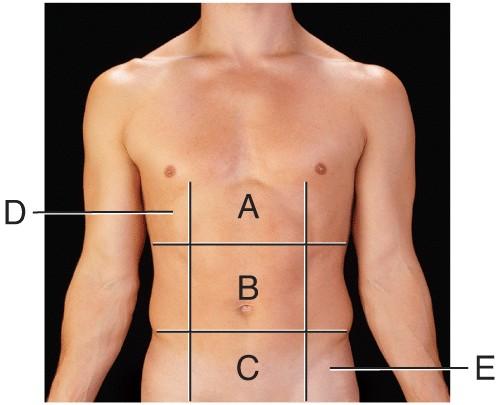

Name the region B.

middle hypochondriac

hypogastric

epigastric

Umbilical

Umbilical

Name the region A.

epigastric

umbilical

right hypochondriac

hypogastric

epigastric

Name the region E.

left hypochondriac

right lumbar

epigastric

left iliac

left iliac

Name the region C.

middle iliac

epigastric

umbilical

hypogastric

hypogastric

Name the region D.

Right Hypochondriac

Left Hypochondriac

epigastric

Right Lumbar

Right Hypochondriac

The liver is found in the region labeled:

A